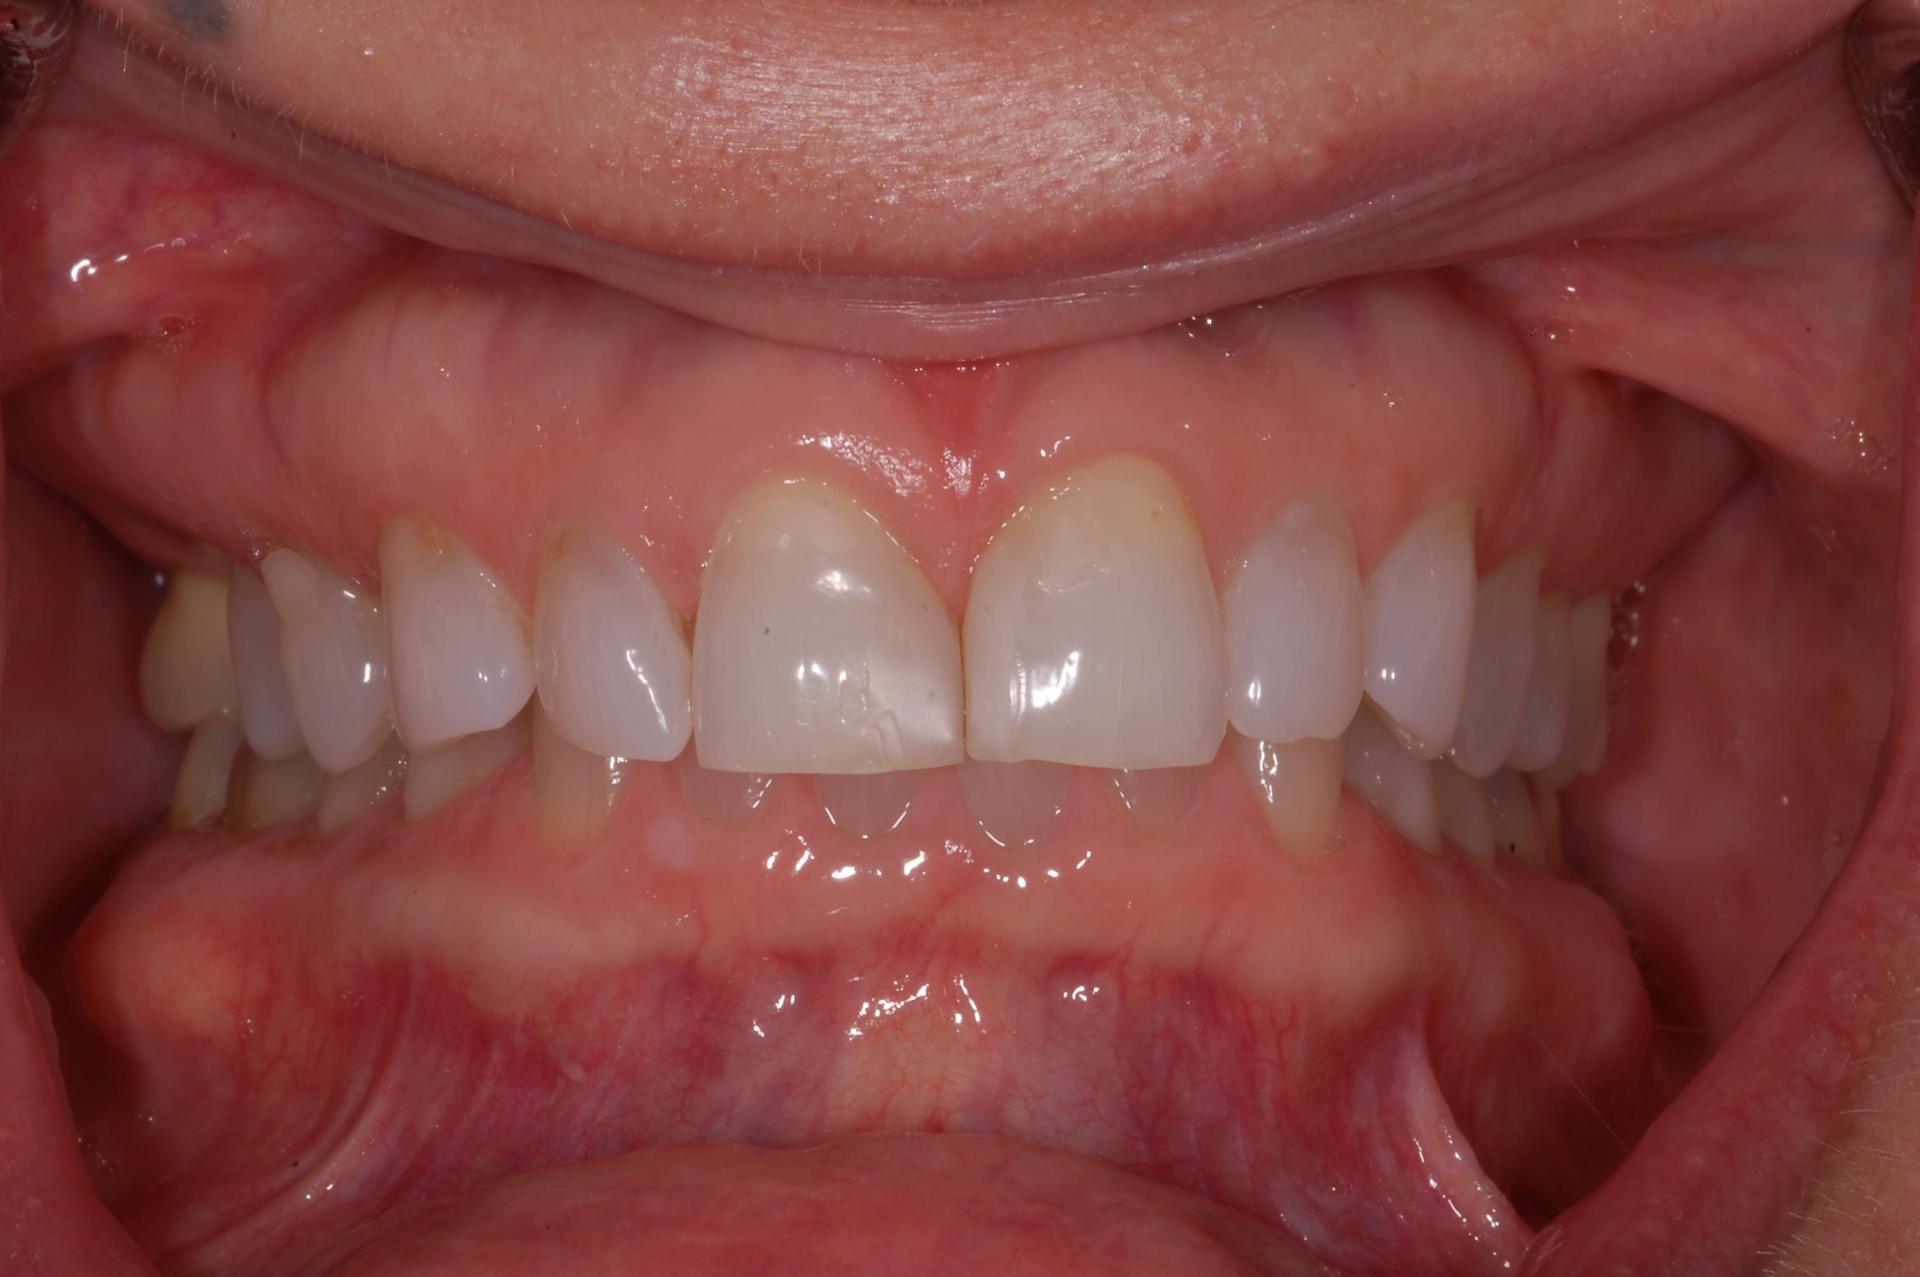

Resin Bonded Restorations (Composites)

This case illustrate a minor touch up with resin bonding. This is an alternative option when the patient does not want extensive treatment. One visit and no

anesthetic!